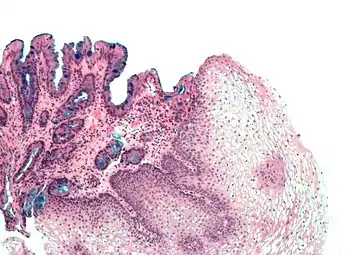

H&E stain of biopsy of normal esophagus showing the stratified squamous cell epithelium.

Section of the human skin showing the stratified squamous epithelial surface, referred to as the epidermis. The layer of keratin here is named the stratum corneum.

A stratified squamous epithelium consists of squamous (flattened) epithelial cells arranged in layers upon a basal membrane. Only one layer is in contact with the basement membrane; the other layers adhere to one another to maintain structural integrity. Although this epithelium is referred to as squamous, many cells within the layers may not be flattened; this is due to the convention of naming epithelia according to the cell type at the surface. In the deeper layers, the cells may be columnar or cuboidal.[1] There are no intercellular spaces. This type of epithelium is well suited to areas in the body subject to constant abrasion, as the thickest layers can be sequentially sloughed off and replaced before the basement membrane is exposed. It forms the outermost layer of the skin and the inner lining of the mouth, esophagus and vagina.[2]

In the epidermis of skin in mammals, reptiles, and birds, the layer of keratin in the outer layer of the stratified squamous epithelial surface is named the stratum corneum. Stratum corneum is made up of squamous cells which are keratinized and dead. These are shed periodically.